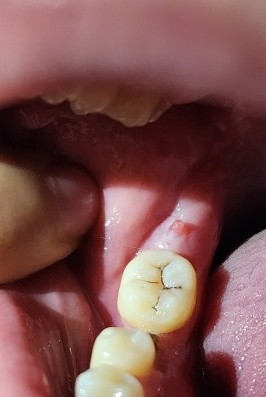

잇몸에 돌기 이거 무엇인가요? 너무 거슬립니다ㅠㅠ

다름이 아니 몇 주전부터 오른쪽으로 씹을때마다 윗니가 아래 잇몸을 씹는거 같이 자꾸 잇몸을 건드려 아래잇몸이 통증이 있었습니다. 그래서 아 교정이 필요하구나 한 줄 알고 며칠 냅뒀는데 오늘 거울 확인해보니 이렇게 돌기가 생겼습니다. 이 돌기는 무엇인가요? 확인 부탁드리겠습니다

• 1번 째 사진

사랑니 등으로 인해서 잇몸에 자극을 받게 되면 해당 부위에 물집 등이 생길 수 있습니다.

이런 자극으로 인해서 잇몸이 증식될 수 있는데 이런 경우에는 간섭되는 원인을 제거해 주면 해결되는 경우가 있습니다.

정확한 확인을 위해서 치과에서 진료를 받아 보는 것을 권유 드립니다